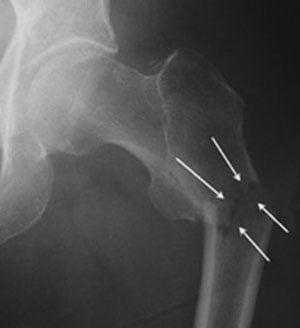

г. перелом шейки на рентгенограмме, д. схематическое изображение остеосинтеза шейки винтами.

Суть заключается в особой технике винтовой фиксации. Винты ввинчиваются у вертелов, проходят внутри шейки параллельно ее поверхности и заканчиваются в центральной части головки бедренной кости.

Начальная и конечная точки выбраны не случайно, так как в этих местах наибольшая плотность костной ткани. Это гарантирует высокую стабильность винтов и прочную фиксацию отломков. То, что нужно для срастания (консолидации) отломков.

Практика показывает, что лучший эффект остеосинтеза винтами достигается при опорных переломах по классификации Pawels I — II и относительно небольшом смещении отломков: Garden I , II .